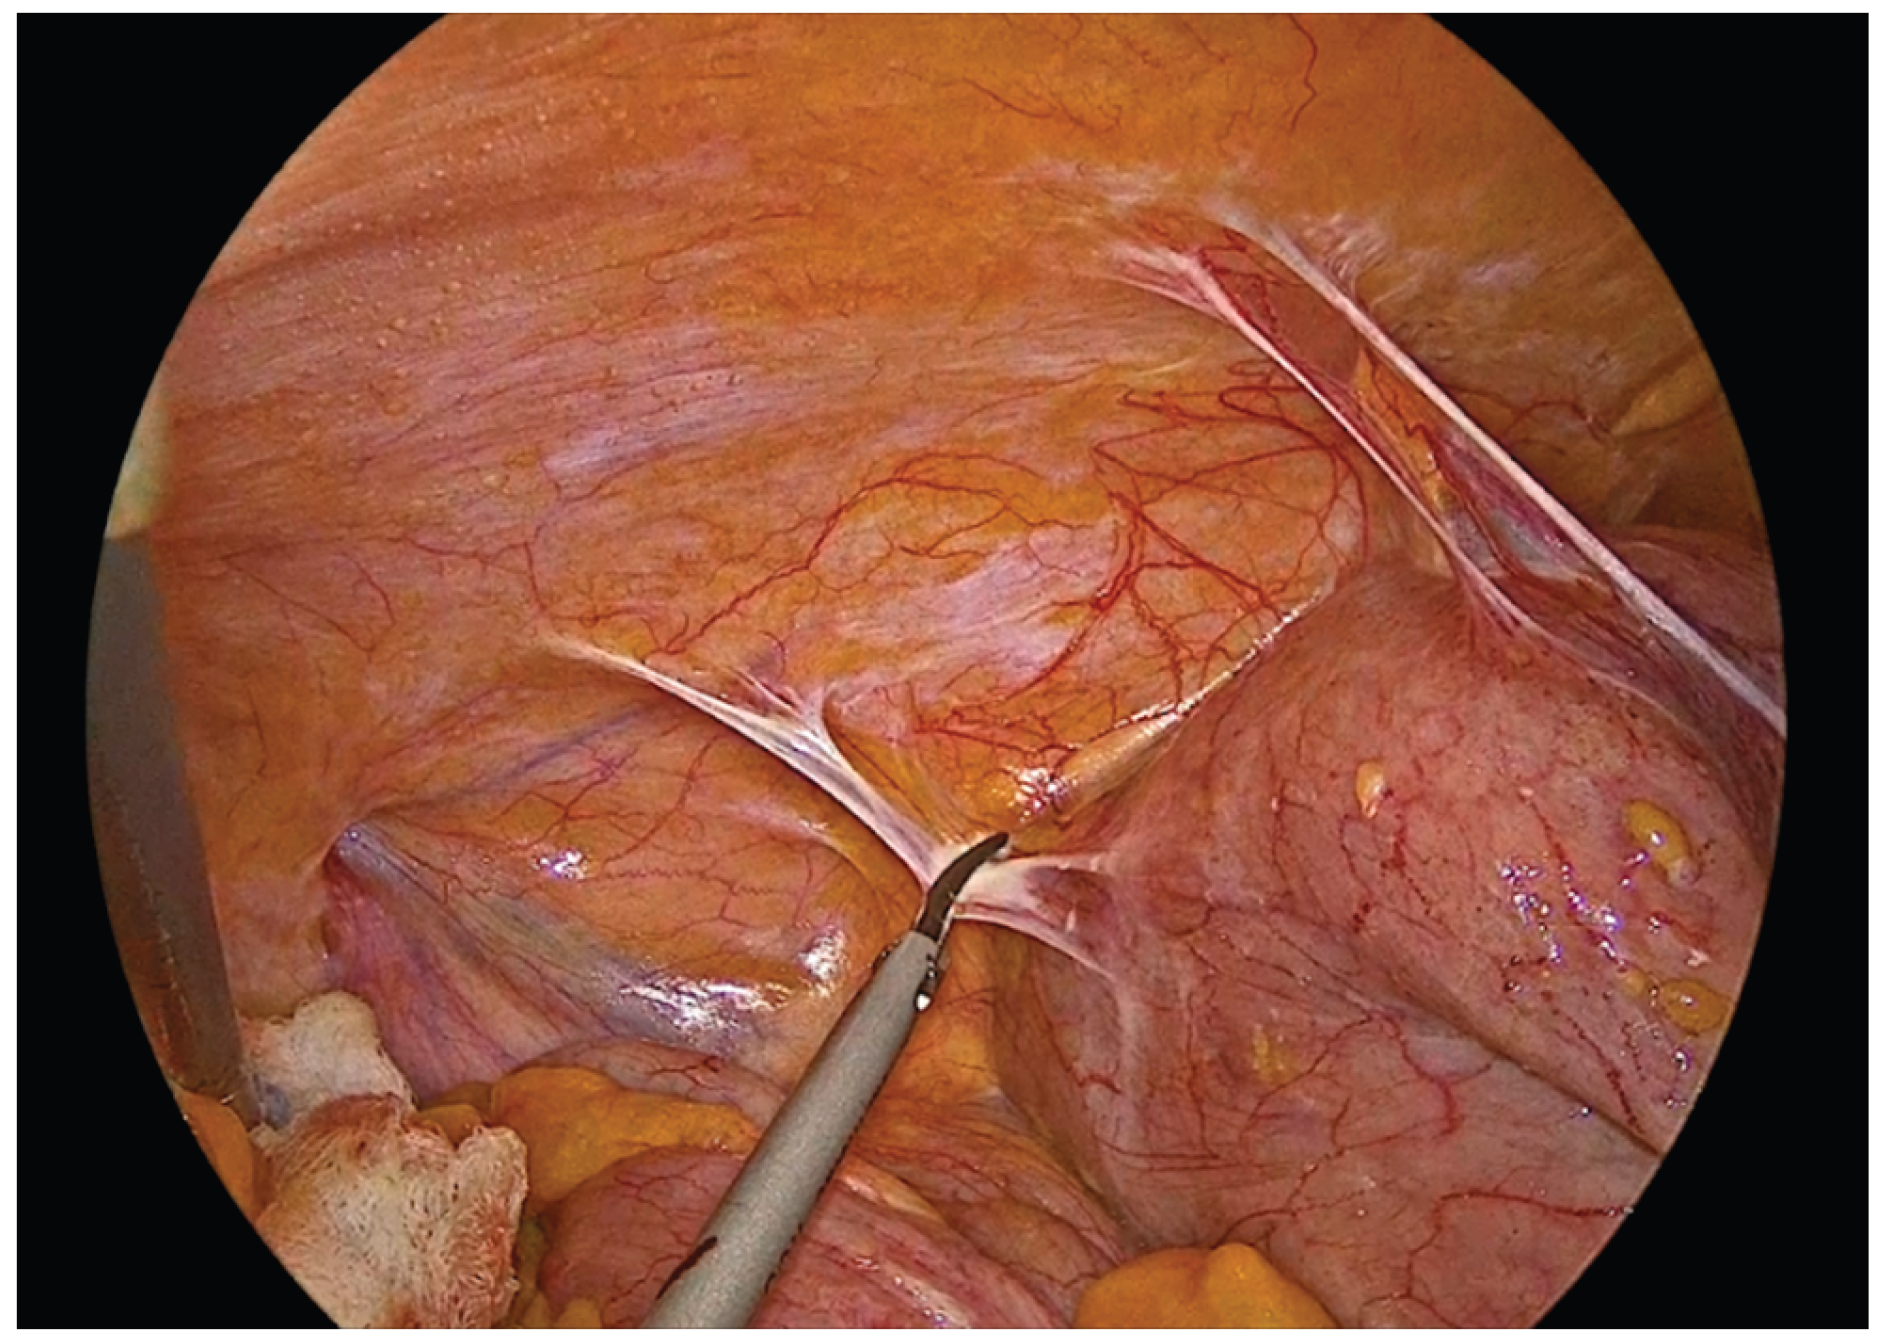

The transverse colon and terminal ileum are aligned in an isoperistaltic, side-to-side orientation, approximately 5 cm proximal to the stapled ends using barbed No.3-0 suture 15cm long. A single - layer handsewn intracorporeal anastomosis is then fashioned using a Vicryl No.3-0 suture 34cm long.

Figure 5. Alignment and positioning of the terminal ileum and transverse colon in an isoperistaltic, side-to-side configuration.

The anastomosis begins with a continuous seromuscular layer using a barbed 3-0 non - absorbable suture, extending for approximately 8 to 10 cm, providing reinforcement and support to the anastomosis.